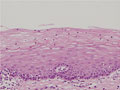

Histology (HE stain, high power): Intact cervical mucosa. The differentiation from basal to surface layer is evident. No atypical cells or koilocytosis apparent.